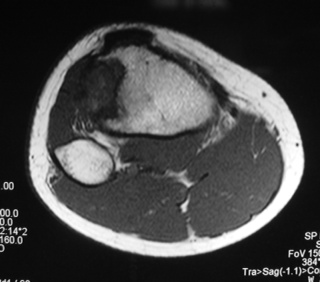

Fig. 4

Fig. 5

Fig. 6

Fig. 7

Fig. 4-7: MR imaging of a benign fibrous histiocytoma of the proximal tibia demonstrates a heterogeneous high signal intensity and low signal intensity with surrounding sclerotic bone on T2-weighted images. T1-weighted images show low signal intensity. No soft tissue mass is visible.